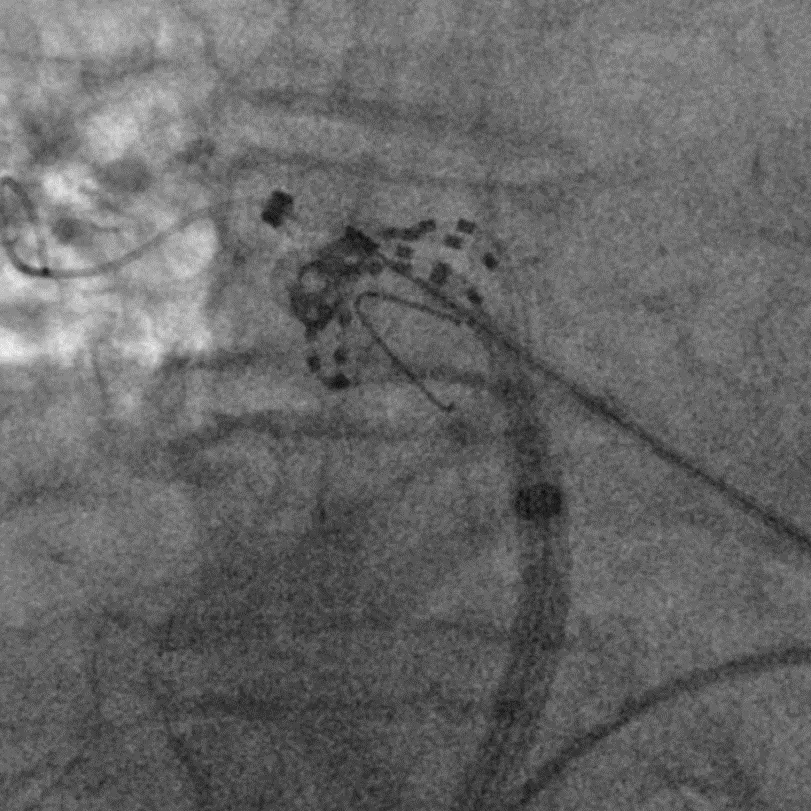

手术过程

手术在全麻下进行,消融策略涵盖双侧肺静脉、左房后壁及上腔静脉,总计消融73个位点,累计消融时间仅146秒。术中活化凝血时间(ACT)维持在250-300秒,未出现并发症。消融结束后,患者仍为房颤心律,经电复律成功转为窦性心律,手术顺利完成。

六瓣花导管呈网篮及花瓣形态放电